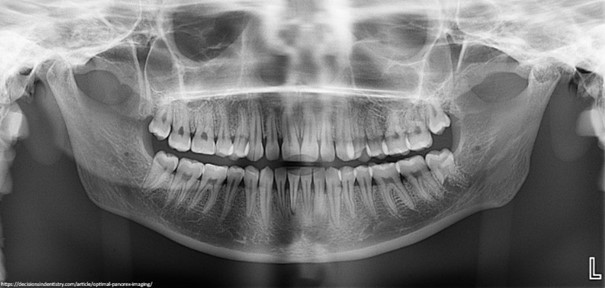

Na przeciwko mnie siedzi pani doktor. Na początku pyta o rzeczy nie do końca związane z zębami. Padają pytania o choroby, o leki, które przyjmuję, ewentualne uczulenia. Wysilam umysł, żeby niczego ważnego nie pominąć. Dalej, od słowa do słowa dochodzimy do przyczyny mojego zgłoszenia bezpośrednio związanego już z zębami. Dużo, bardzo dużo pytań. Niektórych już nawet nie pamiętam. Dentystka próbuje rozwikłać mój przypadek. Na koniec unosi znacząco brwi i oznajmia, że do całościowej diagnostyki potrzebuje jeszcze zdjęcia pantomograficznego.

Idę do pokoju obok. Na moje barki zarzucono szalenie ciężki fartuch. Stoję w środku jakiejś maszyny. Zagryzłem coś plastikowego. Zamarłem w bezruchu, podczas gdy część tego urządzenia obraca się dookoła mojej głowy. Trwa to chwilę.

Wracam do gabinetu. Na ekranie komputera pojawiły się już moje zęby. Zdjęcie czarno-białe. Nic porywającego. Dentystka wnikliwie je analizuje. Następnym etapem jest badanie twarzy i szyi. Nagle fotel zaczyna się odchylać. Ktoś powalił mnie na łopatki za pomocą małego guzika. Otwieram buzię i czuję jak powietrze muska moje zęby. Dentystka wpatruje się w małe lusterko, niczym w zaczarowane zwierciadło. Błysnęły jeszcze flesze, jak w prawdziwym studio fotograficznym. Po przeglądzie mojej jamy ustnej przedstawia swój plan. Pokazuje na zdjęciach, co ją niepokoi. Tłumaczy, co możemy zrobić dzisiaj, a co na dalszych wizytach. Pyta się, czy mam jakieś pytania, czy się na to zgadzam. Oczywiście mam ich mnóstwo. Na szczęście na wszystkie uzyskuje odpowiedź.

Zdjęcia fotograficzne często służą do planowania leczenia, ale są również świetnym sposobem na komunikację z pacjentem. Można na ich podstawie omówić dany problem oraz pokazać wykonaną procedurę. Zdjęcia rentgenowskie obrazują wszystko to, co jest niewidoczne gołym okiem. Stanowią bardzo ważną część w diagnostyce, leczeniu oraz monitorowaniu postępów leczniczych. Najczęściej wykonywane są zdjęcia zębowe i ortopantomograficzne. W wielu przypadkach niezbędna i niezwykle pomocna jest tomografia stożkowa (CBCT).